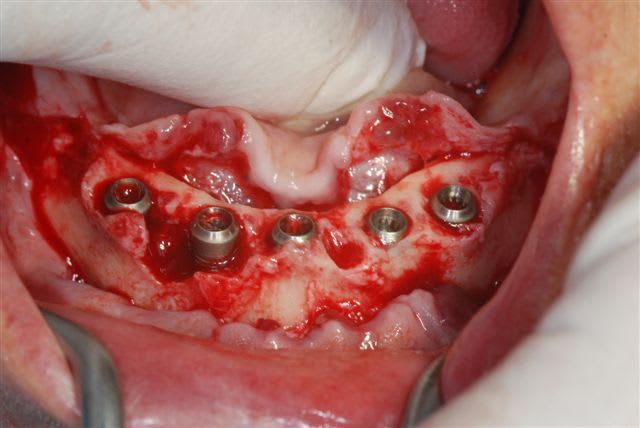

un petit cas clinique de cet après midi:

la pano post op

j'avais prévu de faire une MCI mais le manque de stabilité primaire des 2 implants côté droit m'en a dissuadé.

membrane biomend extend stabilisée par 2 petites vis de 4 mm de long de chez esasy implant. Os autogène et un peu de bio-os mélangé pour combler le defect.